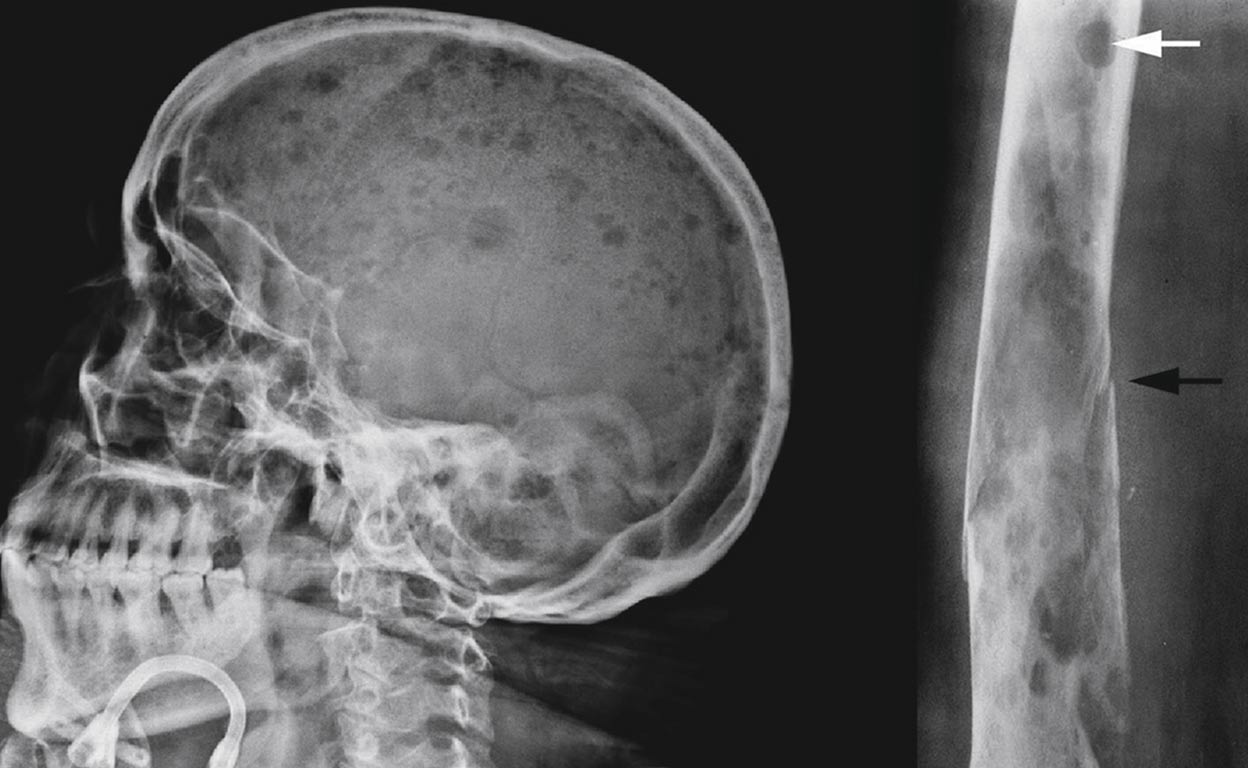

Sirviéndose de una variante neutralizada del virus del sida, un grupo de científicos liderados por el doctor Carl June (en la foto, junto a Emma) lograron reprogramar el sistema inmune de varios pacientes con leucemia linfoblástica severa para combatir el cáncer.

Modificar el VIH

El primer paso consiste en manipular el virus del sida desactivando algunos de sus genes e introduciendo una mezcla de ADN humano, de ratón, de vaca y otros virus.

Reprogramar las células T

Después de extraer del paciente millones de células T (un tipo de glóbulos blancos vital para la respuesta inmunitaria), estas son expuestas al virus inactivo del VIH, que invade las células inyectándoles el nuevo material genético.

Atacar las células cancerígenas

Cuando se devuelven al cuerpo del paciente, las células T reconocen y destruyen las células B, un tipo de linfocitos afectados por la leucemia. Solo hay un problema. destruyen tanto las células B cancerígenas como las sanas.

Crear una memoria celular

Las células T modificadas se multiplican creando células con memoria que continuarán destruyendo futuras células B. La inmunoglobulina (un anticuerpo), administrada por vía intravenosa, permite a los pacientes vivir sin células B sanas.